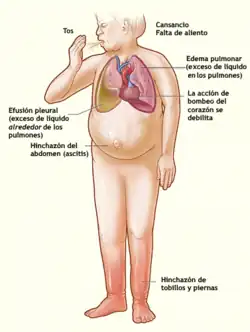

Cuadro clínico

Los síntomas dependen grandemente del lado del corazón que esté predominantemente afectado. Semiológicamente se puede clasificar la Insuficiencia Cardiaca (IC) como IC izquierda o derecha (según la cámara afectada). Esta clasificación es teórica, ya que en la clínica los síntomas, por lo general, se sobreponen.

Síntomas

En una IC Izquierda, el ventrículo izquierdo (VI) tiene dificultad para expulsar la sangre, lo cual provoca un aumento de presión dentro del VI. Dado que el lado izquierdo del corazón bombea sangre proveniente de los pulmones, cualquier fallo en el movimiento anterógrado de la sangre desde el ventrículo izquierdo se transmitirá «hacia atrás» y provocará congestión pulmonar, y «hacia delante» causará una disminución del flujo sanguíneo a los tejidos. Como consecuencia aparecen signos y síntomas predominantemente respiratorios, característicos de este síndrome: la dificultad respiratoria, siendo el síntoma más frecuente de la IC, denominada disnea, en casos más severos aparece aún en reposo. Es frecuente también la ortopnea, que es una forma de disnea al reclinarse o acostarse, así como la disnea paroxística nocturna, que son ataques nocturnos de dificultad respiratoria y en casos severos un cuadro de edema pulmonar agudo, todo lo cual conlleva a una facilidad a la fatiga. La pobre circulación de sangre por el cuerpo causa mareos, confusión y sudoración profusa (diaforesis) con extremidades frías en el reposo.

Edema

El lado derecho del corazón bombea sangre que proviene de los tejidos en dirección hacia los pulmones con el fin de intercambiar dióxido de carbono (CO2) por oxígeno (O2). El aumento de presión del lado derecho provoca dificultad en el retorno venoso y congestión sanguínea en los tejidos periféricos. Ello causa edema de los miembros inferiores, que suele llegar a cubrir hasta el abdomen, momento en que se denomina anasarca.

En casos más severos, se provoca hipertensión portal, con los síntomas asociados a ella: acúmulo de líquido en el abdomen (ascitis), aumento del tamaño del hígado (hepatomegalia), síntomas gastrointestinales, etc. La IC-derecha raramente aparece sola, generalmente se asocia a una IC-izquierda previa, que es la principal causa de la falla del lado derecho del corazón.

Estertores pulmonares

La elevada presión de llenado del corazón derecho que causa la distensión venosa suele verse acompañada de edema de las extremidades inferiores. Ambos fenómenos se deben al incremento de la presión venosa y el edema aparece cuando por motivo de la elevada presión el líquido sale de los vasos sanguíneos y se colecta en los tejidos, fundamentalmente —por efecto de la gravedad— en los miembros inferiores.